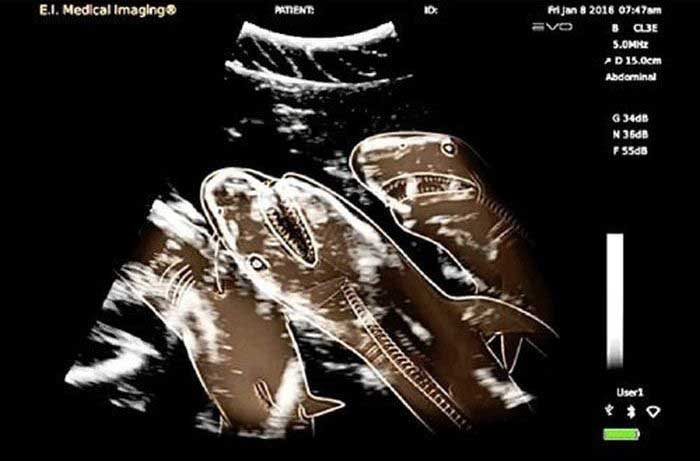

妊娠した様々な動物たちをレントゲン(X線)写真で見てみたギャラリー。サメ、ネズミ、犬、猫など。一度に複数の子供を出産する犬や猫などは特に怖い事に…。

1. サメ